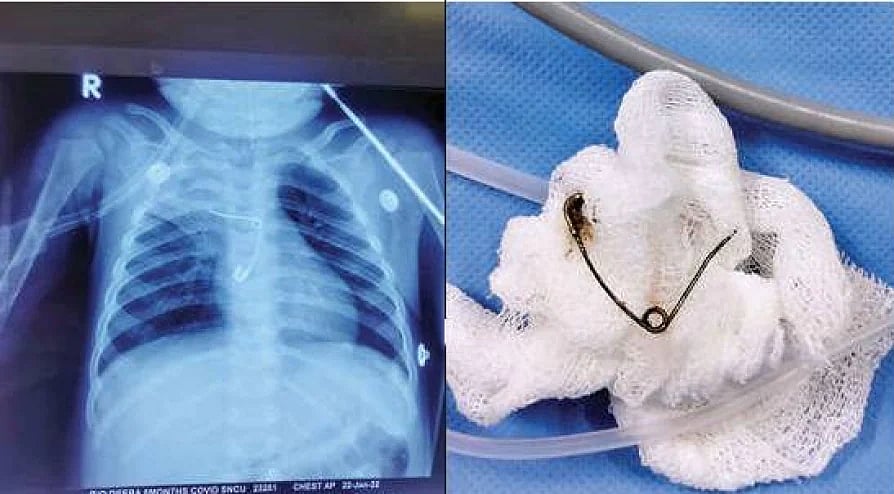

ஊக்கினை விழுங்கிய 8 மாத குழந்தைக்கு புது வாழ்வை கொடுத்த திருச்சூர் மருத்துவக் கல்லூரி மருத்துவர்கள்!

14 February 2022, 10:28 AM